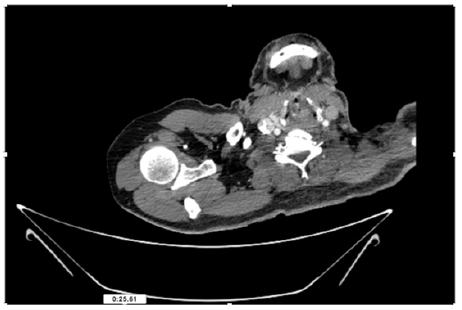

55-years-old chronic smoker had acute, severe pain in the right upper limb for one week; it was cold upto mid arm with skin discoloration. He also noticed numbness and weakness of movement of elbow joint. He underwent below elbow amputation in February 2023 for acute ischemia of left upper limb. He was a current chronic smoker; 15 pack year. General condition was weak; temperature was normal; blood pressure was 100/60mmHg; heart rate was 92/minutes with sinus rhythm; SpO2 was 97% on air; heart was normal. In lower extremities, all peripheral pulses were intact. Local Examination of right upper limb revealed as follows: tenderness; coldness; discoloration; decreased motor function and sensory modalities. Axillary, brachial and radial pulses were not palpable. Hand-held Doppler failed to detect any signal in arterial system; therefore, we arranged for emergency embolectomy. complete occlusion of right upper limb arterial system Full blood count showed high hemoglobin (14.6gm%); normal total WBC and platelet count. Coagulation profile was normal. Parenteral unfractionated heparin, antibiotics, tramadol, proton-pump inhibitors, anti-platelets and HMG CoA reductase inhibitors were given. Doppler ultrasound demonstrated complete occlusion of right upper limb arterial system. CT Angiogram illustrated occlusion of subclavian artery downwards on both sides. Figures 1-14 shows complete occlusion of right subclavian artery without collaterals. On Day ‘2’ of admission, the patient passed black tarry stool for 3 times. However, the vital signs were stable; blood pressure was 100/60mmHg; heart rate was 92/min; SpO2 was 97% on air; the abdomen was soft and not tender. Above elbow amputation was done on Day ‘2’ of admission. Intra-operative findings were as follows: (1) no active bleeding at brachial artery; (2) thrombosis along brachial artery; (3) muscle color and consistency were not healthy.

Figure 4: CT Angiogram at neck showing normal brachio-cephalic trunk, common carotid artery, and narrow right subclavian artery.

Figure 5: CT Angiogram at neck showing normal brachio-cephalic trunk, common carotid artery, and narrow right subclavian artery.

Figure 6: CT Angiogram at neck showing brachio-cephalic trunk, common carotid artery and narrow right subclavian artery.

Figure 7: CT Angiogram at neck showing brachio-cephalic trunk, common carotid artery and narrow right subclavian artery.